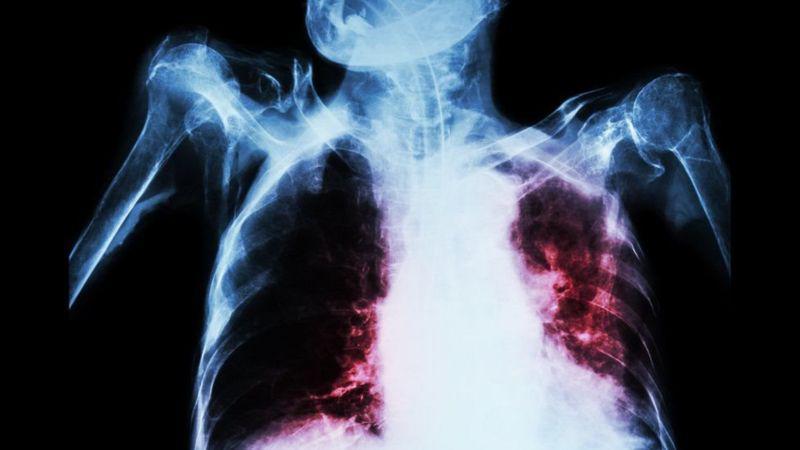

క్షయ వ్యాధి సాధారణంగా ఊపిరితిత్తులకు (pulmonary TB) సోకుతుంది. కానీ ఇది శరీరంలోని ఏ అవయవానికైనా సోకే అవకాశం ఉంది (extra pulmonary TB). (గోరు, జుట్టు తప్ప.)

- ఊపిరి తిత్తులకు సోకితే, దగ్గు, ఆయాసం, తెమడలో రక్తం పడడం కనిపిస్తుంది.